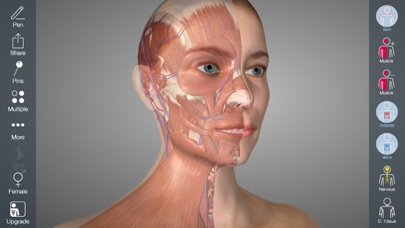

Downloading Essential Anatomy 5 IPA for iOS is a convenient and useful way to explore the world of human anatomy right from the comfort of your iPhone or iPad. This app provides a comprehensive and detailed view of the human body, allowing users to interact with various systems and structures. With stunning 3D graphics, it offers a visually captivating experience that aids in understanding and learning about the complexities of the human body. Whether you are a medical student, healthcare professional, or someone with a general interest in anatomy, Essential Anatomy 5 IPA is a must-have app that provides a wealth of knowledge at your fingertips. The app’s intuitive interface and easy navigation make it accessible to users of all levels of expertise. With just a few taps, you can delve into different layers of the body, explore various organs, muscles, and bones, and gain a deeper understanding of human anatomy. Download Essential Anatomy 5 IPA today and elevate your knowledge and appreciation of the human body.

The Essential Anatomy 5 IPA for iPhone is an incredible tool for medical students, professionals, and anyone interested in learning more about the human body. This app provides a comprehensive and detailed 3D model of the human anatomy, allowing users to explore and study different parts of the body with ease. With its user-friendly interface and interactive features, users can zoom in, rotate, and examine every angle of the human body, from bones and muscles to organs and systems. The app also provides in-depth information about each structure, making it a valuable resource for studying and understanding the intricacies of human anatomy. Whether you’re a medical student preparing for exams or simply curious about the wonders of the human body, the Essential Anatomy 5 IPA for iPhone is an essential tool to have at your fingertips.

Essential Anatomy 5 IPA allows users to interact with the 3D models, zooming in and rotating them to explore every angle. The user-friendly interface makes navigating through the app a breeze, and the intuitive controls ensure that anyone, regardless of their level of expertise, can easily explore and understand the complex anatomical structures.

5. Personalization and Customization

Essential Anatomy 5 IPA allows you to personalize your learning experience by creating bookmarks, notes, and pins to mark important areas or structures for future reference. The app also offers customization options, allowing you to choose from various light and dark themes to suit your preferences or circumstances.